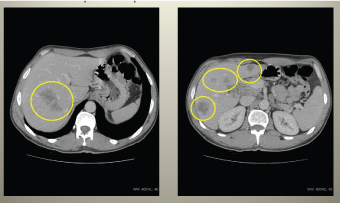

A 49-year-old male presented with abdominal pain and defecation problems. Colonoscopy examination showed ulcerating tumour 8 cm over the anal opening, histologically-tubular adenoma, CEA - 28.4 ng/ml, CA 19-9 - 31.6 U/ml. A week later local and systemic dissemination of process was radiologically diagnosed (Figures 1-3).

Figure 2. Abdominal CT showing retroperitoneal lymphadenopathy and massive metastatic process in hepatic lobes.